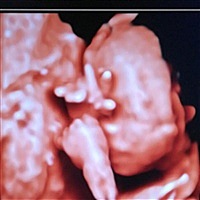

孕15周+3天

孕39周+6天